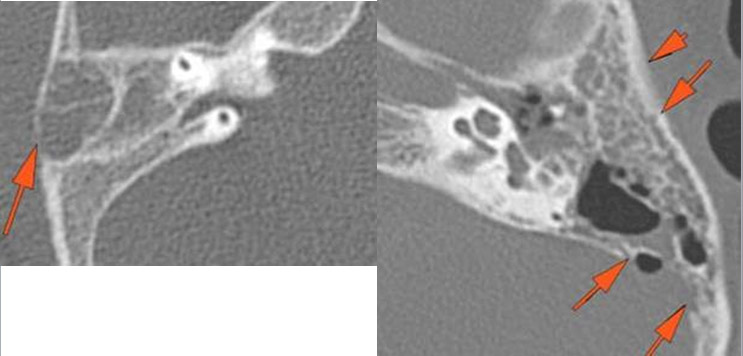

There is a subperiosteal abscess along the outer margin of the mastoid portion of the temporal bone.